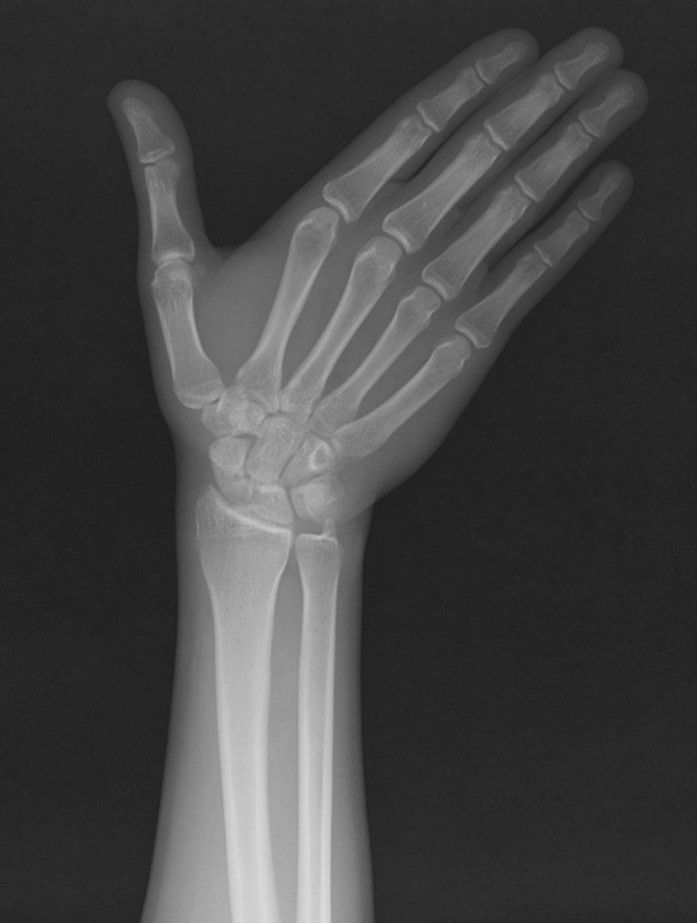

Case 14 - Sol Lunat Cyst

47 yr, male, laborer, right hand dominant

Left wrist pain for 4 years

Pain aggraveted in last 2 months

Pain radiates to arm and has muscle cramp